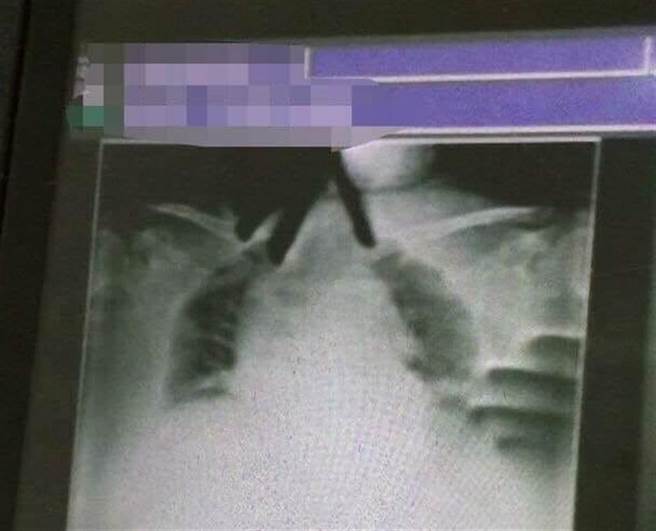

一名網友日前在臉書社團「靈異公社」分享醫師好友發生的詭異事件,有個阿嬤在留院觀察時突然喘不過氣、大口呼吸、心律不整、神情驚慌,為了查明呼吸急迫的原因,醫護人員緊急幫阿嬤做了X光。但過了許久仍等不到檢驗室把X光片送到雲端,打電話詢問後沒想到對方說:「嗯…我們覺得片子有點問題,還在討論要不要上傳」。最後在醫師的催促下,拿到了手機翻拍X光片的影像。

讓人毛骨悚然的是,X光片中清楚顯示,在阿嬤脖子及肺部部位出現兩隻手,而且這2隻手拍不出骨頭,沒多久,阿嬤清醒了,睜開眼睛第一句話就緊張地說:「剛剛有人爬在我的上面,一手掐住我喉嚨,一手抓我胸口,讓我好難受…」。

該文引起許多網友討論,文章也釣出當年的主治醫師留言,證實照片沒造假,醫師表示這位病人入院的時候肺部根本沒問題,是當天早上突然變得超級喘,不得已只好先插管。至於病人為何當天情況會突然變差醫師也不明白,進ICU時,裡頭的主治醫師還問這個病人為什麼要插管,結果3天就拔管出ICU,並順利出院。